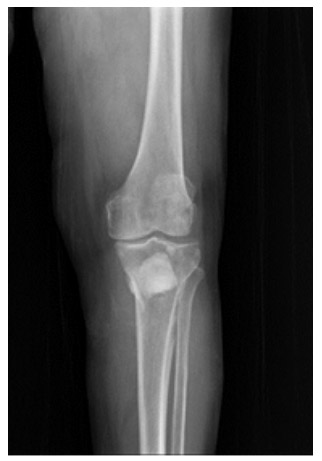

Postoperative: The image shows the tumor being removed and then filled with bone cement.